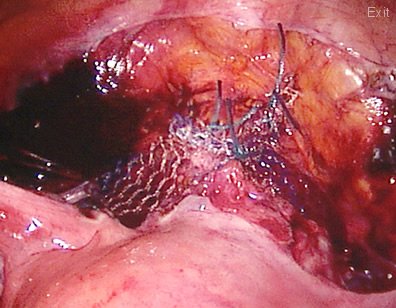

The mesh is being deeply buried "between the cavity and the bones". This will avoid contact of the mesh to the bowels.

The whole of the vagina has been reconstructed including the perineum (area between the introitus and the anus) to provide full support. A "transversal" tape or sling has also been placed under no tension underneath the urethra (opening from the bladder to pass urine) to correct incontinence.